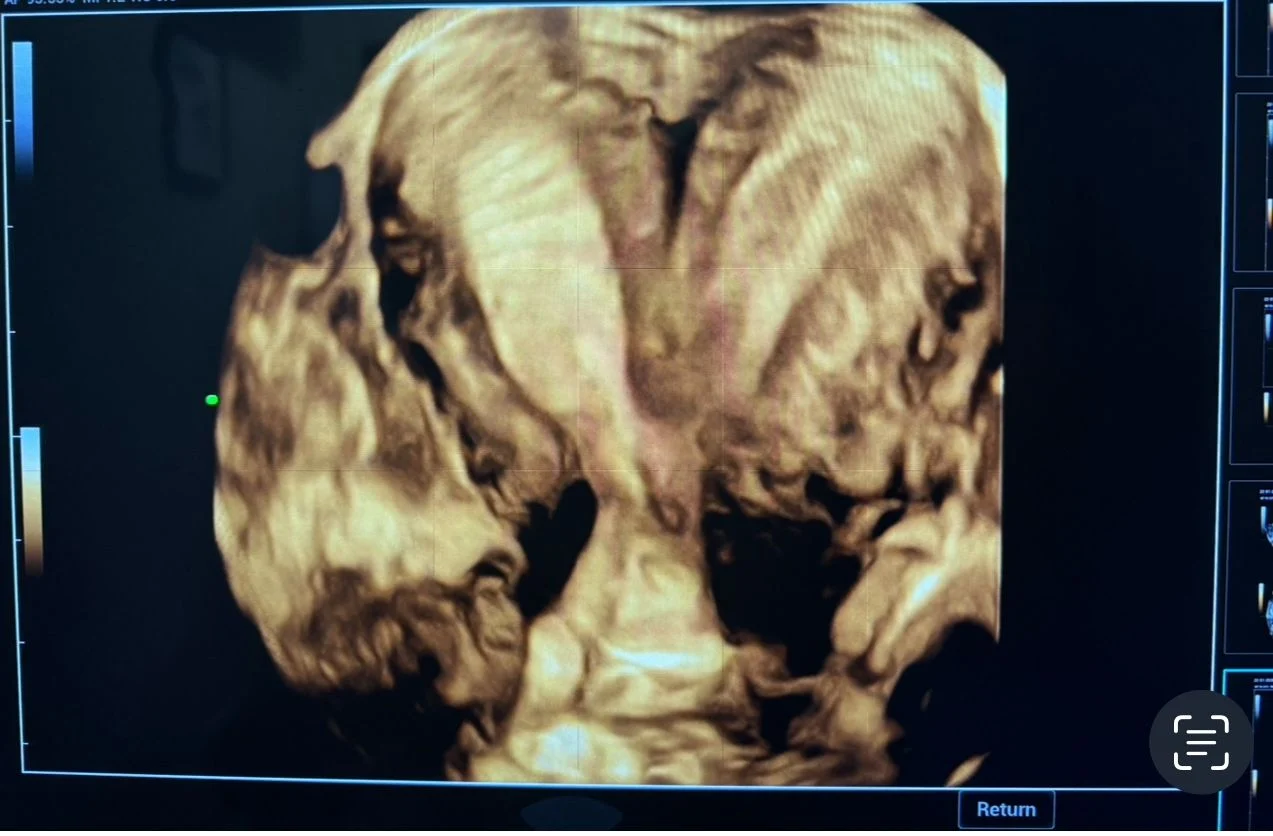

A 3D transvaginal ultrasound examination revealed a congenital uterine anomaly consistent with a bicornuate uterus with features suggestive of uterus didelphys.

- Two well-defined uterine cavities with fundal indentation

- Partial to near-complete duplication of the uterine horns

- External fundal cleft supporting a bicornuate configuration

- Suspicion of duplication extending toward the cervix (differential with uterus didelphys)

3D transvaginal ultrasound plays a crucial role in accurately assessing the external fundal contour and cavity configuration.